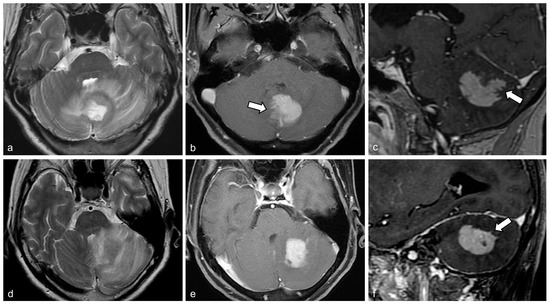

| Concomitant supratentorial lesions | 10 (41.7) | 18 (56.3) | 0.42 |

| Bulging contour | 1 (4.2) | 20 (62.5) | <0.001 |

| Surface involvement | 7 (29.2) | 23 (71.9) | 0.003 |